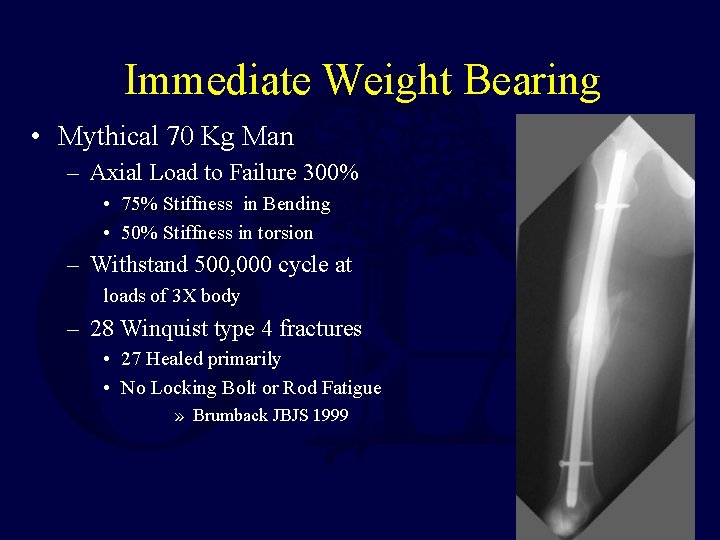

Static Locking of All Femoral IM Nails !!! • Brumback- 1988 – 98% union with Statically Locked Rod

Immediate Weight Bearing • Mythical 70 Kg Man – Axial Load to Failure 300% • 75% Stiffness in Bending • 50% Stiffness in torsion – Withstand 500, 000 cycle at loads of 3 X body – 28 Winquist type 4 fractures • 27 Healed primarily • No Locking Bolt or Rod Fatigue » Brumback JBJS 1999